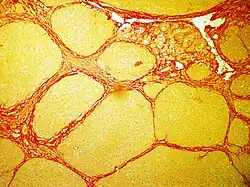

In histology, sirius red staining is used in various domains of diagnostic to observe fibrosis levels in a lot of cases of inflammation induced by cancer, vascular or metabolic pathologies.[2]

In bright field microscopy the following can be observed:

- The nuclei in yellow

- The cytoplasm in yellow

- Collagen fibers in red

- Muscular fibers in yellow

- Red blood cells in yellow